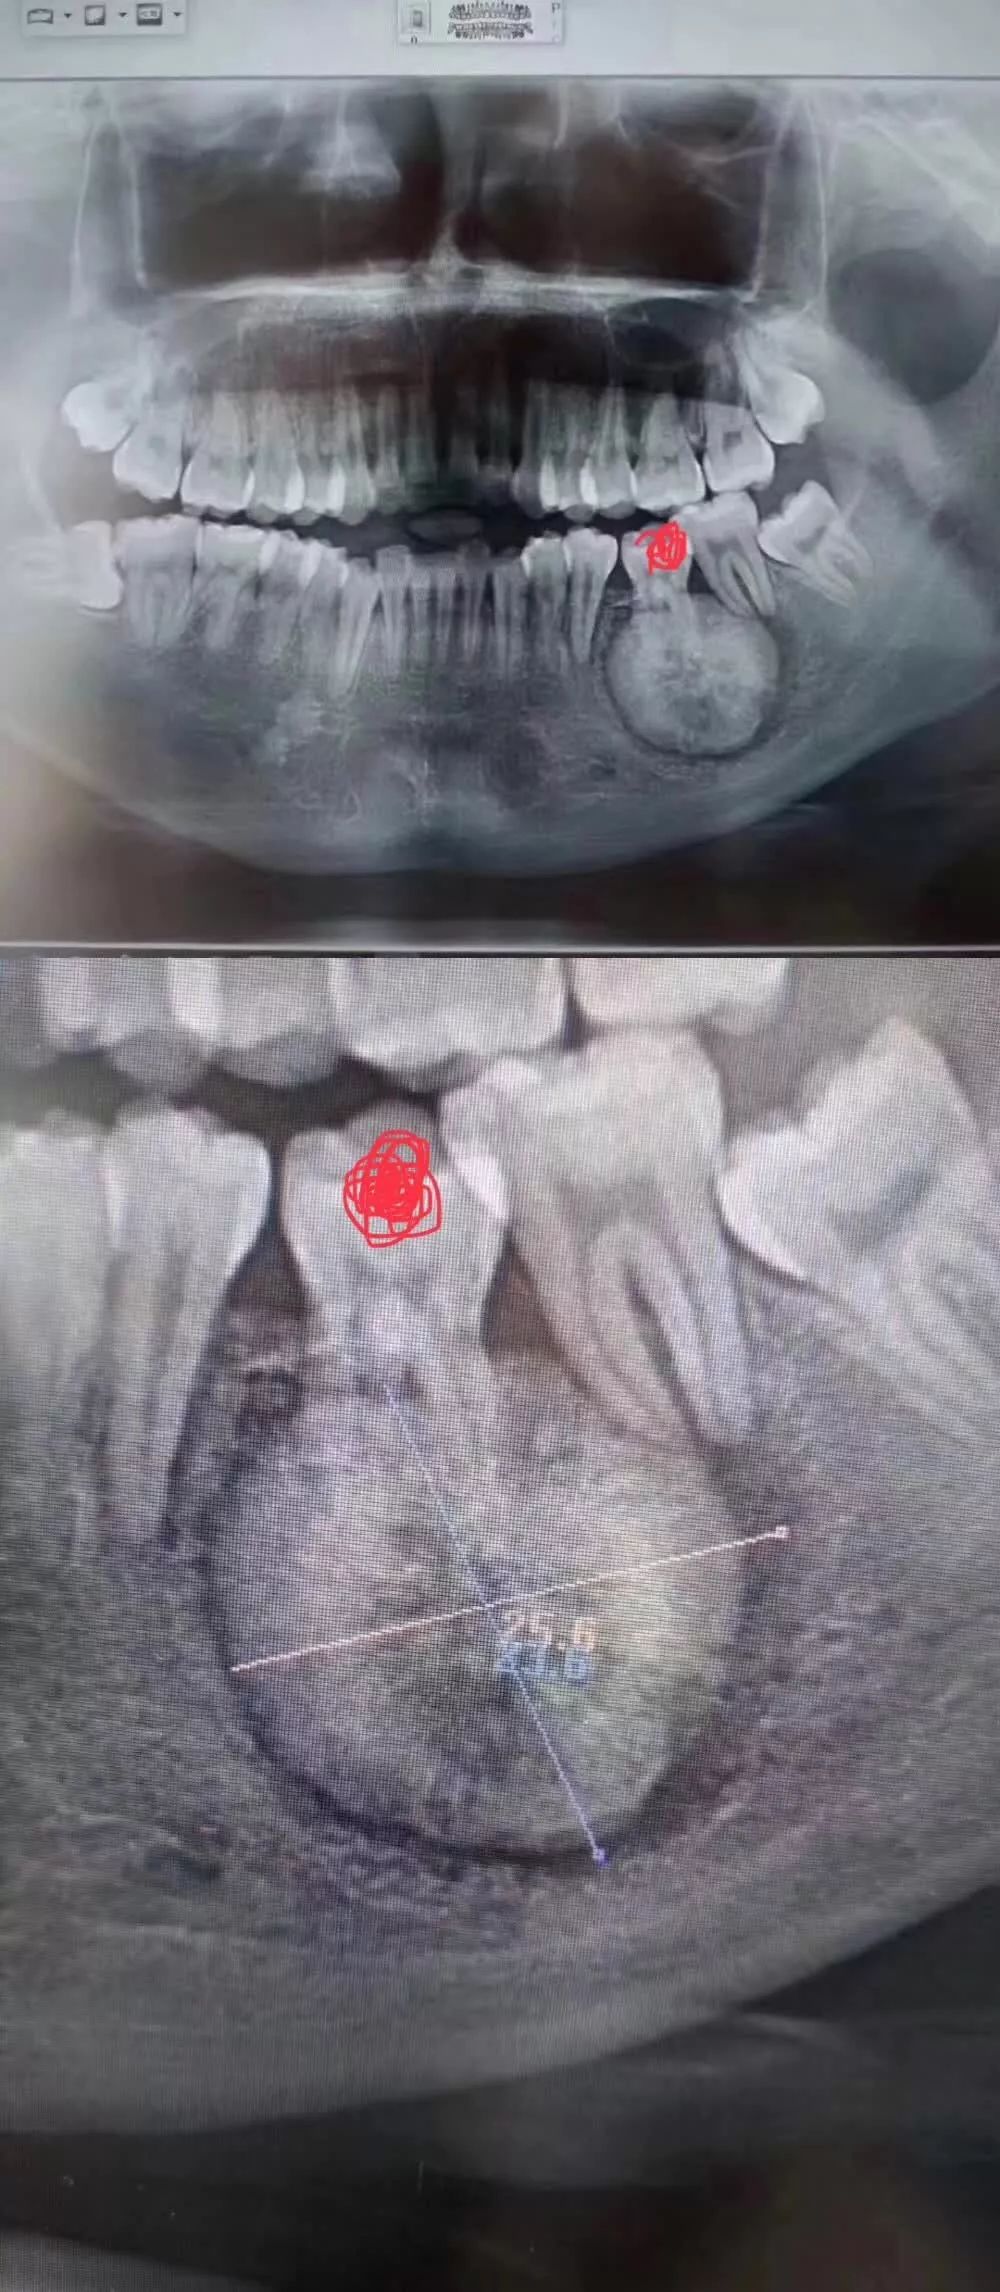

患者是30多岁的年轻男子,红色标记那颗牙松动,要求拔牙,开始嫌麻烦不愿拍片,后来经过再三劝说还是拍了片。结果把所有人包括他自己都吓了一跳。估计是良性,具体还得去医院住院手术做病理检查,所以大家不要忽视一张片子带来辅助检查的重要性。

试想,如果没有拍片,直接贸然拔牙,一旦出现问题......一张牙片,“救”了诊所,也救了患者!